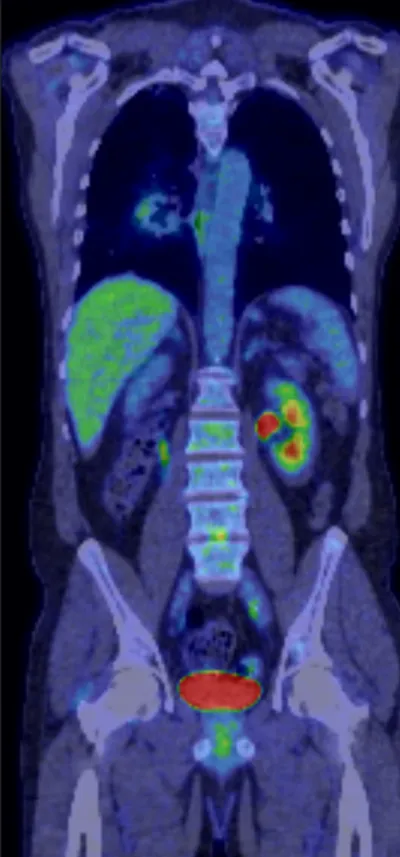

PET Radiology Images

tagged: PET

This collection contains 1 radiology images related to pet, including various imaging modalities such as X-rays, MRIs, CT scans, and ultrasound images commonly used in medical diagnosis and education.